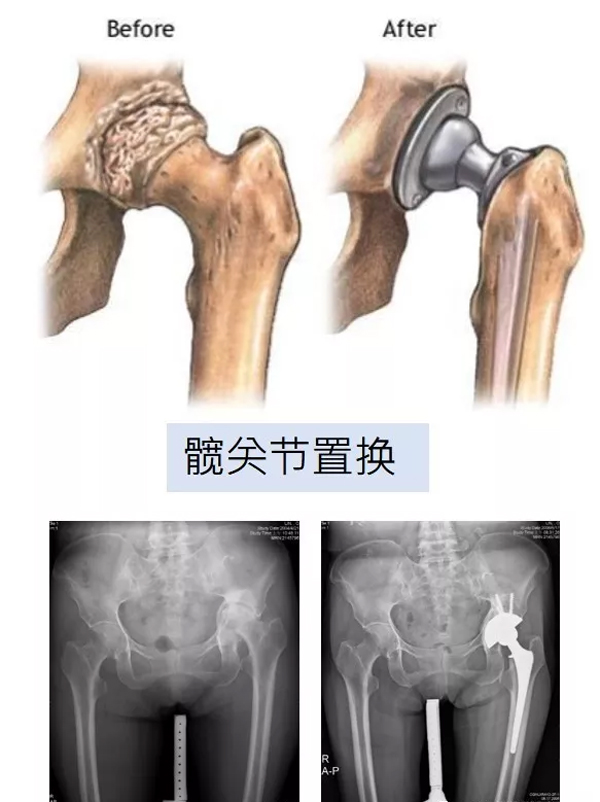

人工关节置换术

是将己磨损破坏的关节面切除,置入人工关节,使其恢复正常平滑关节面的手术。

髋关节及膝关节是人体中大,也常使用的负重关节。关节因老化、外伤或疾病,导致功能缺损,可能会因疼痛影响正常生活,甚至导致行动不便。经使用药物或其他方法仍无法减轻症状时,人工关节置换成为恢复正常行动能力的很佳选择。